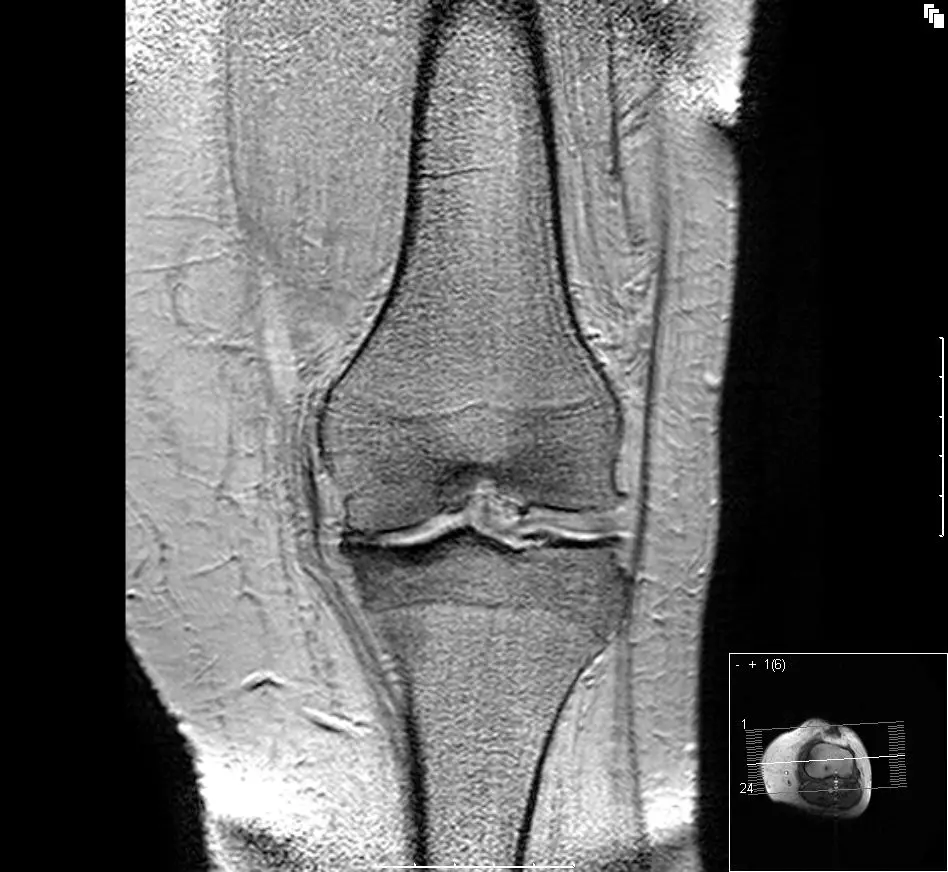

Degradation of the knee cartilage can be brought on by all sorts of causes – trauma, hereditary and developmental factors or even just plain wear and tear – but the result is the same. Without healthy cartilage cushioning the point where the femur sits on top of the tibia, those two bones grind away at each other with the full weight of the body behind them, causing painful and incapacitating damage over time.